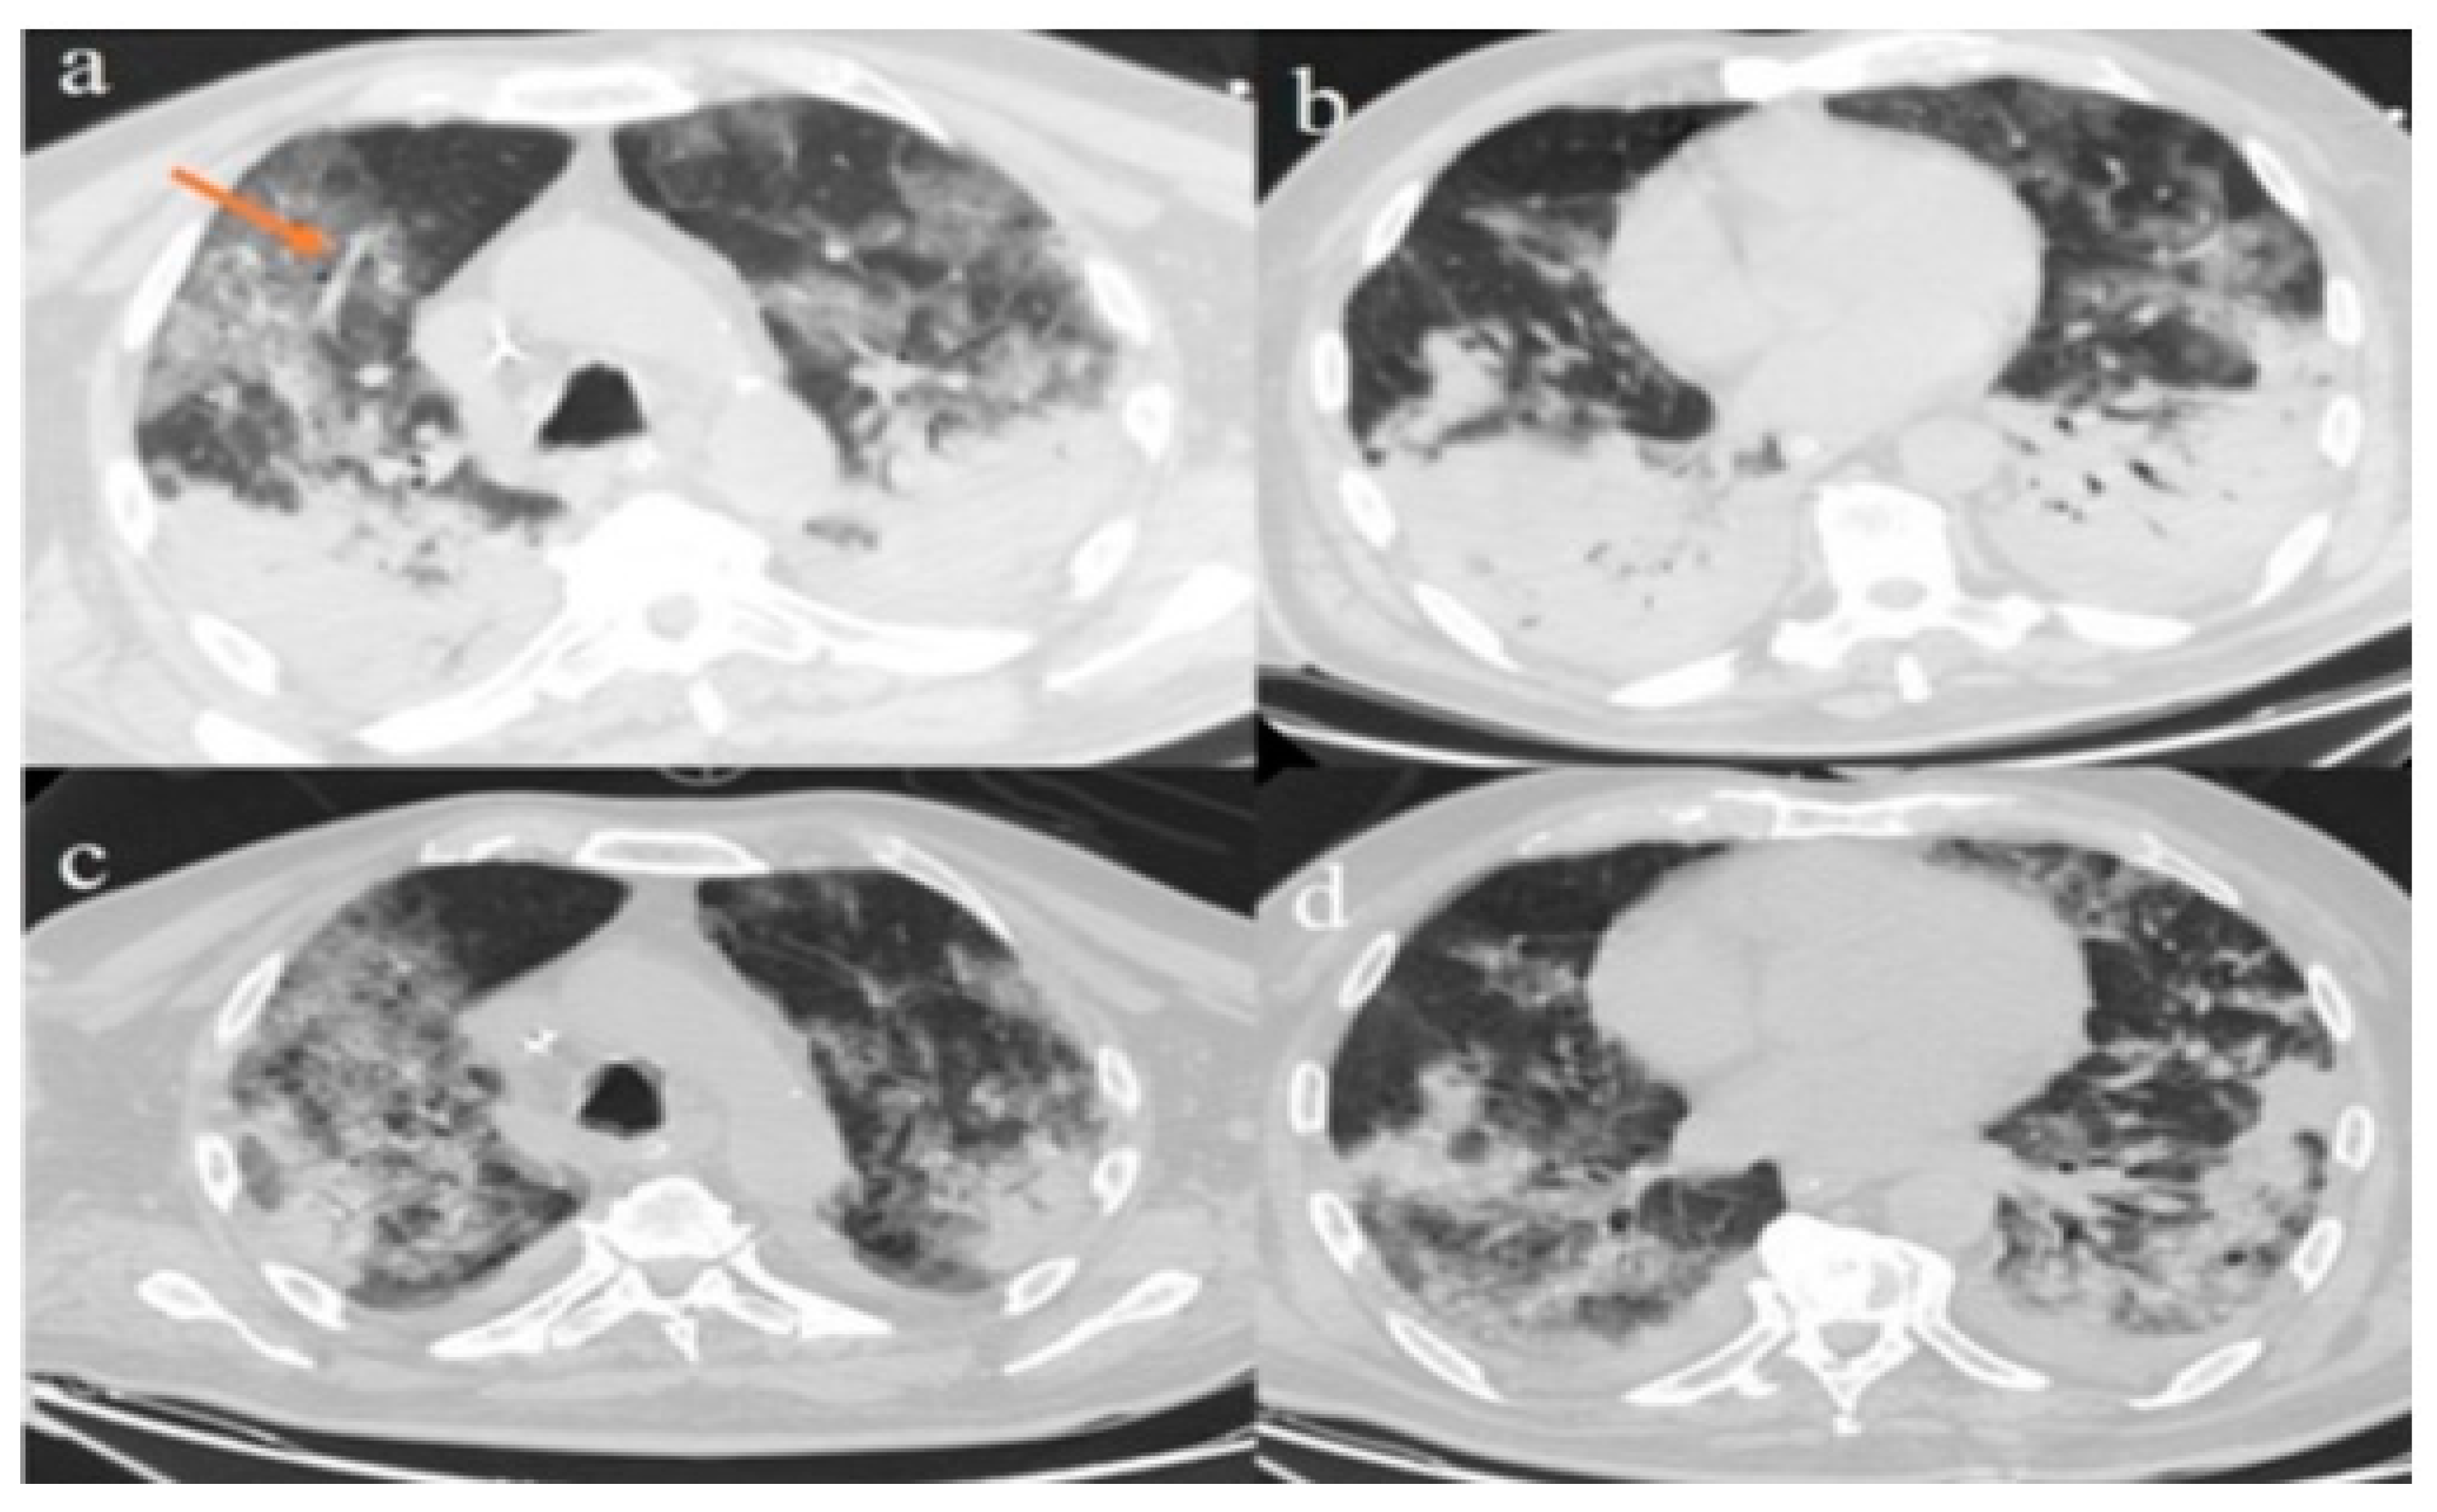

2. Case Presentations

2.1. Case 1

2.2. Case 2